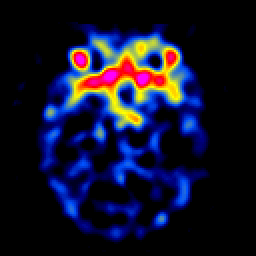

SPECT TL Study #4 -- Slice #19

[Home][Help][Clinical][Tour 1][Tour 2][Tour 3] Slice 19